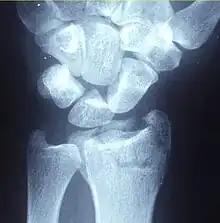

![]() | |

| A Colles fracture as seen on X-ray: It is a type of distal radius fracture. | |